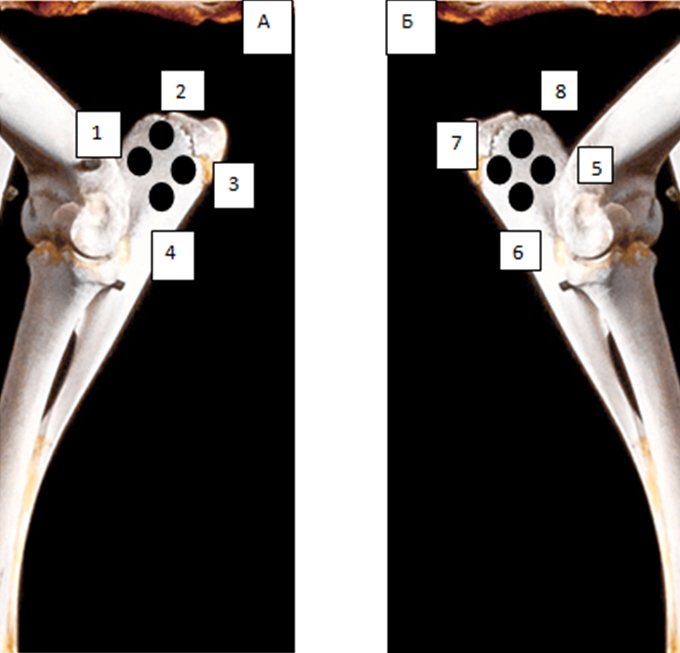

Рис. 1. Поперечный срез микротомографии локтевого отростка овцы

Учитывая выше перечисленные недостатки, поиск новых областей и способов хирургического доступа для создания экспериментальной модели исследования остеопластических материалов является актуальным. Нас заинтересовало использование в качестве экспериментальной живой модели область локтевого отростка передних конечностей овцы. В доступной литературе нами не встречено упоминаний об использовании локтевых отростков овец с целью формирования костных дефектов для оценки регенераторного потенциала остеопластических материалов. Вероятно, это обусловлено боязнью риска травматизма локтевого отростка в ходе формировании дефекта при использовании классического хирургического инструментария – сверл и фрез большого диаметра. Между тем очевиден ряд преимуществ данной области – схожее анатомическое строение и архитектоника с альвеолярной частью челюстей человека. Локтевой отросток имеет наружный кортикальный слой и внутренний, представленный губчатым веществом с костномозговыми пространствами небольшого размера (рис. 1, 2).

Рис. 2. Поперечный срез альвеолярной кости верхней челюсти человека в проекции отсутствующего премоляра (А) и альвеолярная кость нижней челюсти человека в проекции отсутствующего моляра (Б). 3D-КЛКТ